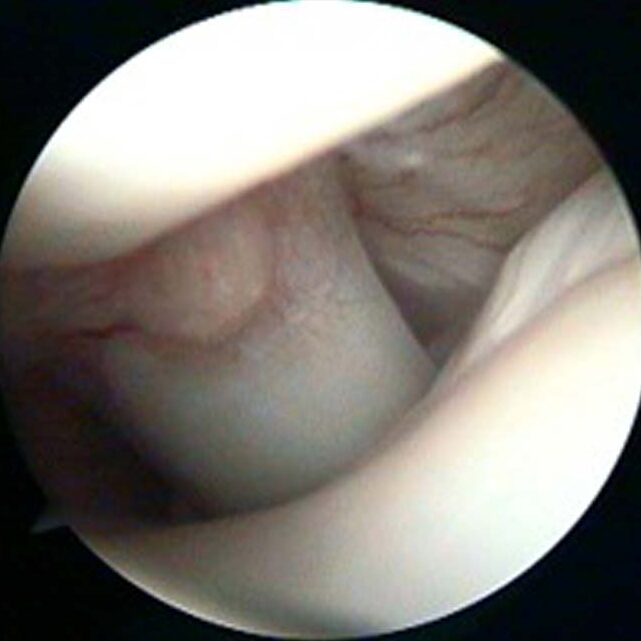

Osteochondritis dissecans is a developmental disorder of larger breed dogs that typically starts to cause signs at 5-7 months of age, but sometimes later. Breeds affected by OCD include giant breeds such as Great Danes and popular breeds such as Labrador and Golden Retrievers, as well as Border Collies. The cause is not clear but it is more common in male dogs. It represents a failure of the joint surface to develop correctly and the cartilage, which lines the joint surface, can become partially detached from the underlying bone; this causes pain and because the cartilage is typically partially detached, the underlying tissue cannot heal.

Recommended treatment for OCD that is causing persistent pain is surgical removal of the loose cartilage and, in our opinion, this is best performed with keyhole surgery (arthroscopy). Arthroscopy minimises trauma to the soft tissues and allows for a rapid recovery. In addition, arthroscopy provides the surgeon with magnification and access to all parts of the joint.